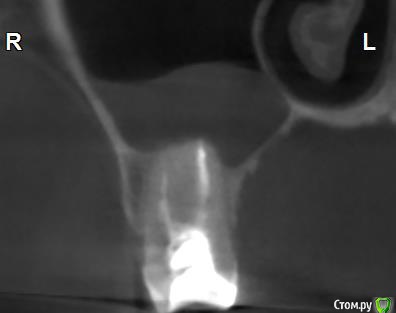

Здравствуйте! Верхний правый шестой зуб пломбировали 3 месяца назад. Примерно месяц назад он начал ныть, после насморка, сначала периодами, а теперь почти постоянно. При постукивание (ощущается не совсем так, как другие зубы) и пальпации десны он не болит. 2,5 месяца назад удаляли кисту из гайморовой пазухи. Может ли быть это какое-то воспаление и есть ли вероятность устранить его какими-нибудь антибиотиками, если да, то как, или может удалить зуб? Если есть воспаление, то какие могут быть последствия если не удалить зуб?

(Снимки с КТ, первые 8(Image) - сделаны сейчас,по 4 в разных проекциях, вторые 8(Before) - сделаны 5 месяцев назад до удаление кисты и повторного пломбирование зуба( до повторного пломбирование он реагировал на горячее, был запломбирован 3 года))

переличили зуб адекватно, во всяком случае по снимкам